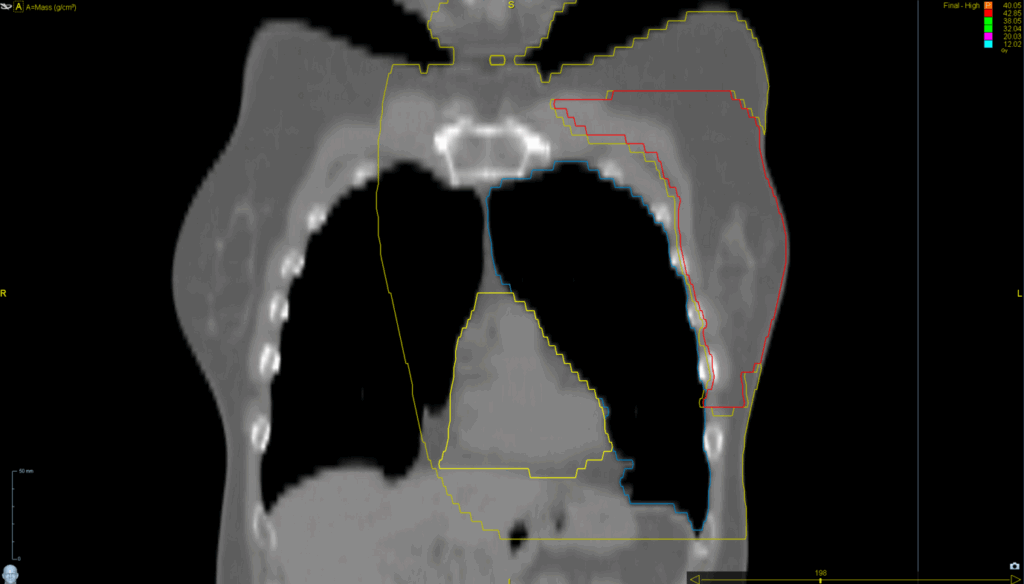

Planning CT Images

PTV(s) Volume, Length

944 cc, 18.3 cm